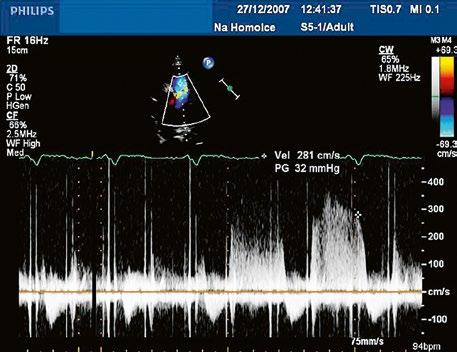

Plastika malformované mitrální chlopně u AVSD může být velmi obtížná, hrozí riziko mitrální stenózy (Obr. 45.23, Video 45.19, Video 45.20, Video 45.21), v některých případech je nutná náhrada mechanickou protézou. Při těžké trikuspidální regurgitaci je indikována i plastika trikuspidální chlopně, při dokumentovaných supraventrikulárních arytmiích MAZE výkon.

Obr. 45.23 Dopplerovský záznam mitrálního průtoku z TEE u pacienta po uzávěru inkompletního AVSD a plastice mitrální chlopně v dětství s reziduální kombinovanou mitrální vadou, mitrální stenózou a regurgitací ( Video 45.19, Video 45.20, Video 45.21)